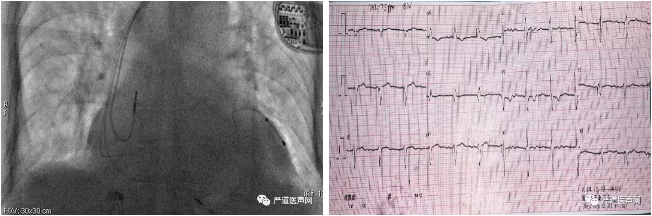

术后影像&术后心电图

患者为81岁女性,诊断房颤、慢快综合征,心衰,心功能IV级,高度房室传导阻滞,完全性左束支传导阻滞,QRS间期156ms, 超声心动图显示:EF:35%,左房44mm,左室52mm。根据患者临床病史及症状, 经过充分的术前评估和术前准备,顾翔教授团队为患者行CRT植入术。

术后,病人通过参数优化,QRS波仅120ms左右,而且术后一周的超声显示EF值已恢复到41%,已经达到了超反应,病人也主诉感觉明显舒服了许多。